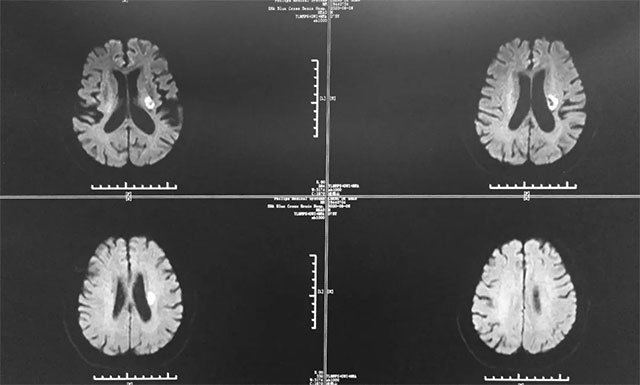

▲ 胡先生多發(fā)性腦梗,情況不容樂觀

今年5月29日,胡先生正坐在沙發(fā)上看手機(jī),突然感覺自己的右腿有些麻木,當(dāng)時想著肯定是坐著看手機(jī)時間太長了,就沒太在意。第二天下午,他一如既往地去廣場跳舞,當(dāng)時右腿還是有些麻木,但不影響跳舞,可是等到晚上8點多時,他明顯感覺不對勁,右腿麻木癥狀較前加重,遂即就診于當(dāng)?shù)亟K省某醫(yī)院。入院后,患者行頭部CT檢查,根據(jù)影像結(jié)果,患者被診斷為多發(fā)性腦梗,并予以相關(guān)對癥治療。

據(jù)戴秀珍主任回憶,胡先生剛?cè)朐簳r其腦梗還是比較嚴(yán)重的,患者屬于多發(fā)性腦梗,并多處血管狹窄,致使其右側(cè)肢體功能障礙。尤其是右側(cè)上肢肢體,近端肢體肌力為2級,其遠(yuǎn)端肢體肌力卻為0級,而且右上肢還伴有神經(jīng)性水腫;其下肢肢體肌力為3級,不能站立和行走,并出現(xiàn)了言語含糊癥狀。